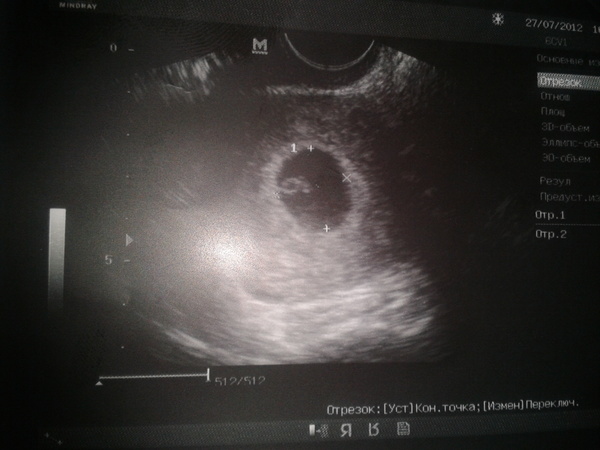

ну если ничего не беспокоит, то конечно лучше не рисковать. У меня просто ЗБ была....поэтому, чтобы спать спокойнее я хожу делаю УЗИ + у меня гематома была, надо было ее проверить.

5 сентября, это уже скрининг будет. Удачи :)